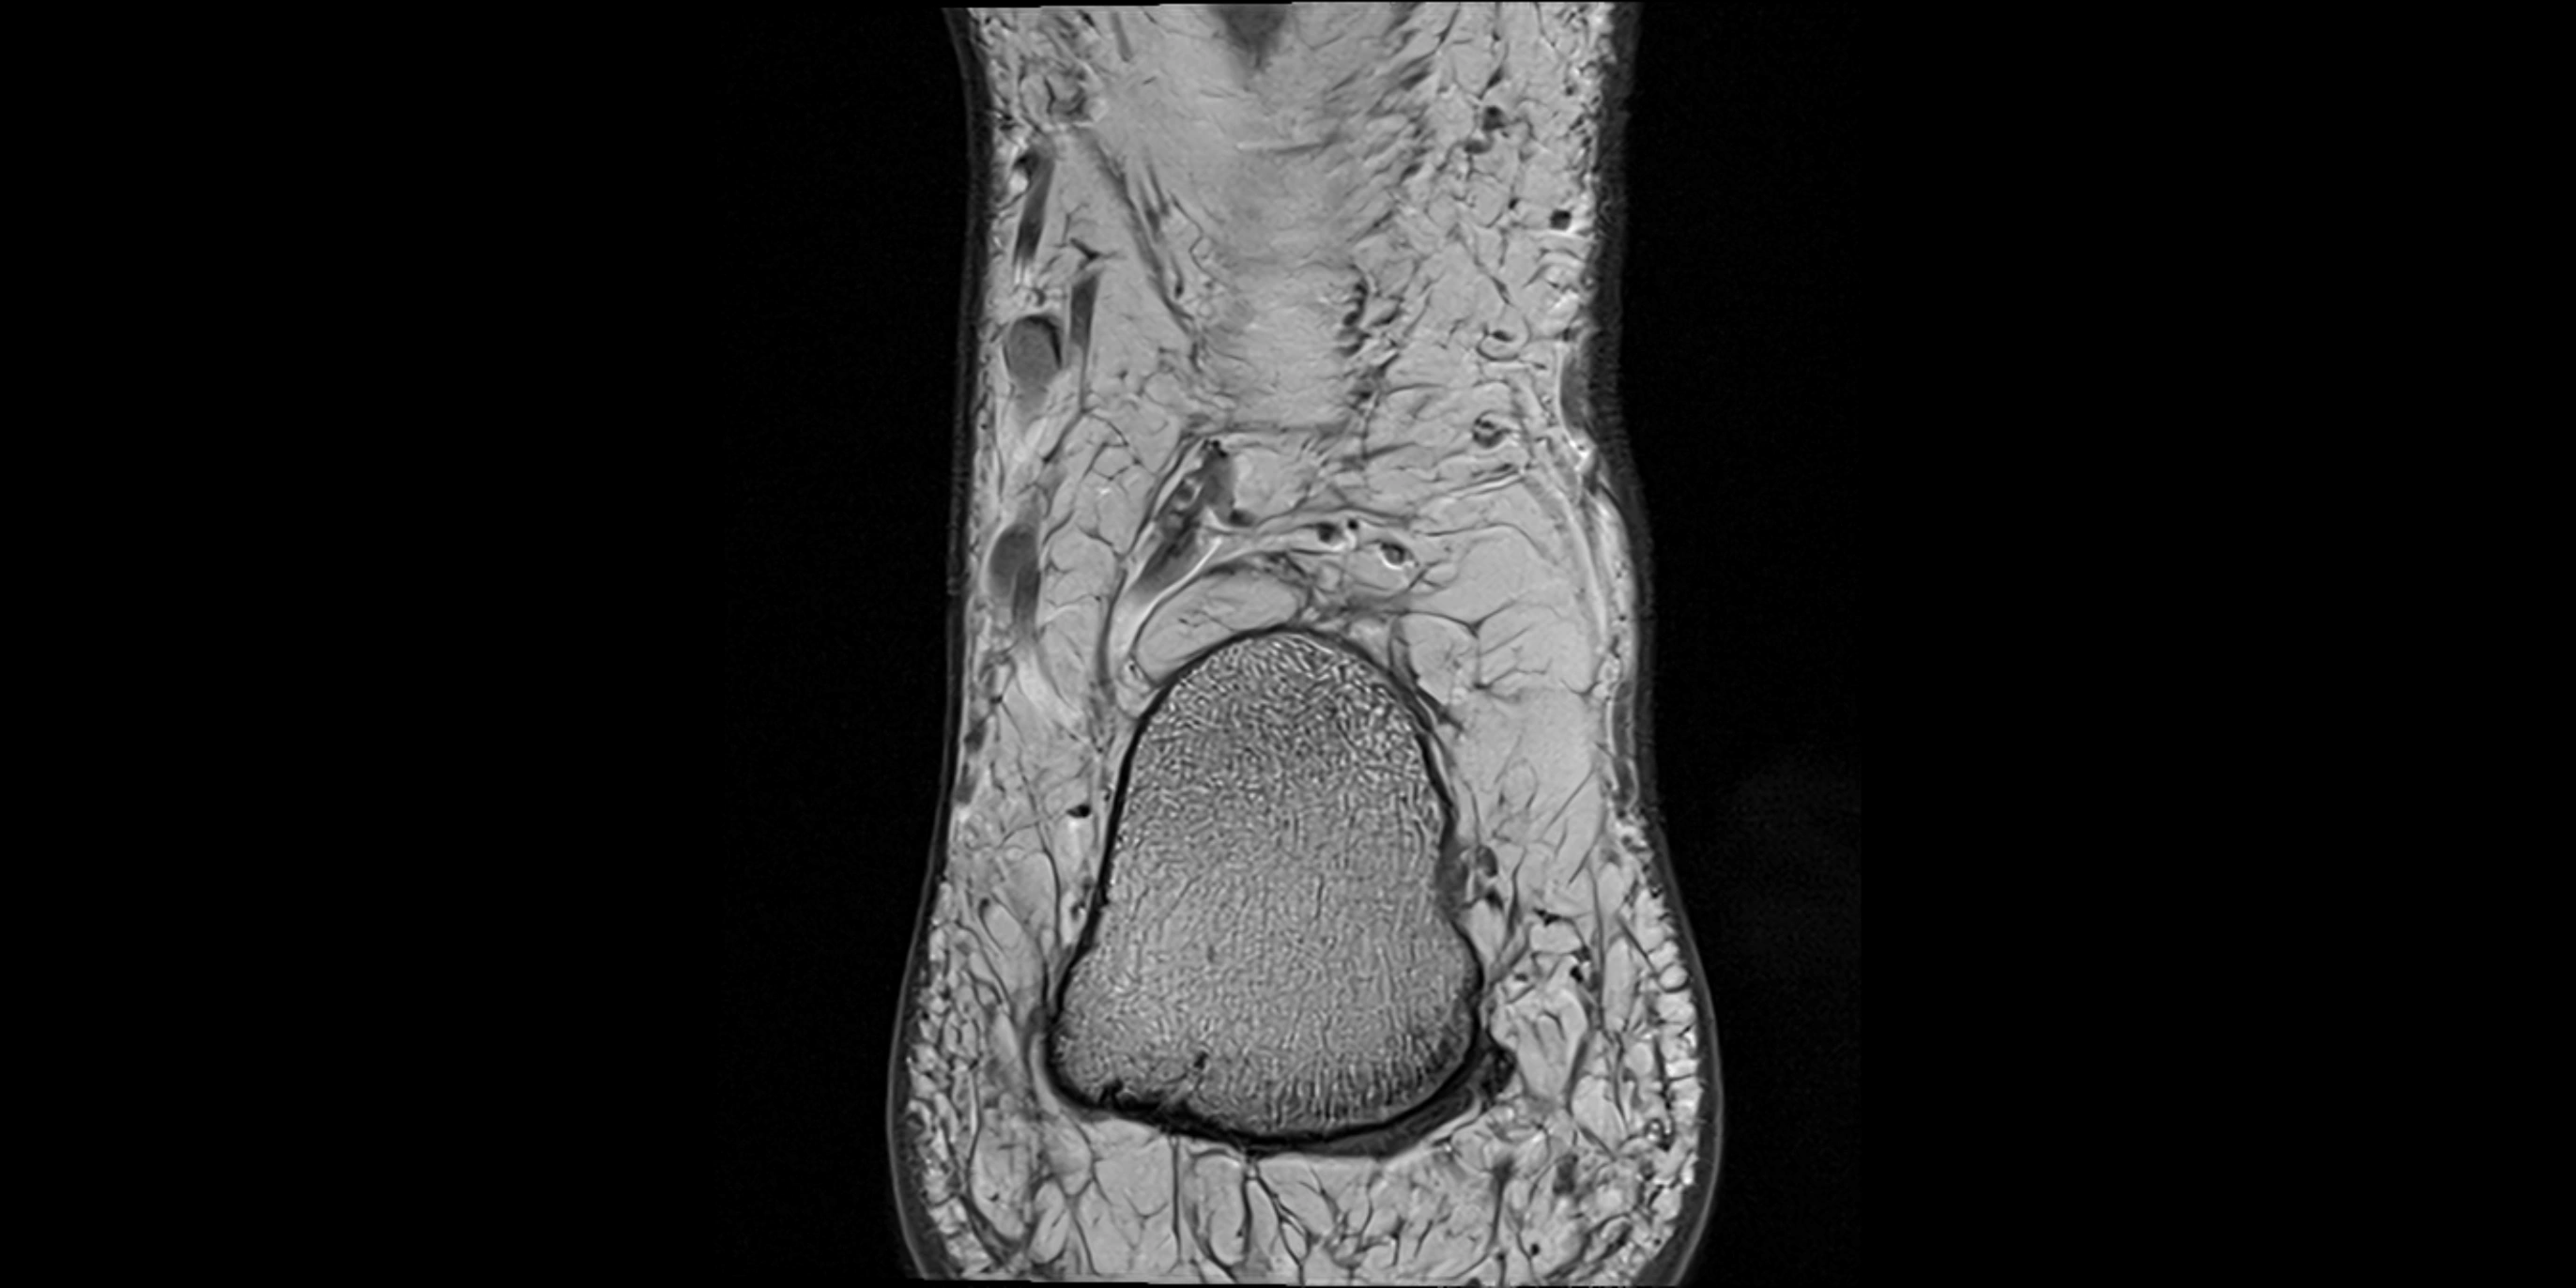

MRI Appearance

• T1-weighted images:

• Muscle belly: intermediate signal intensity with visible fascicular structure

• Tendon: low signal (dark linear band) extending to the base of the fifth toe

• Surrounding fat: bright, outlining tendon and muscle course

• Partial tear or tendinopathy: focal thickening with increased intermediate signal intensity

• T2-weighted images:

• Normal muscle: intermediate-to-low signal, slightly darker than on T1

• Normal tendon: very low signal (dark), smooth and continuous

• Pathology: bright hyperintense foci along the tendon or myotendinous junction representing inflammation, edema, or partial tear

• Peritendinous fluid or sheath thickening appears as bright hyperintensity